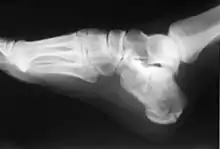

Calcaneus fracture X-ray